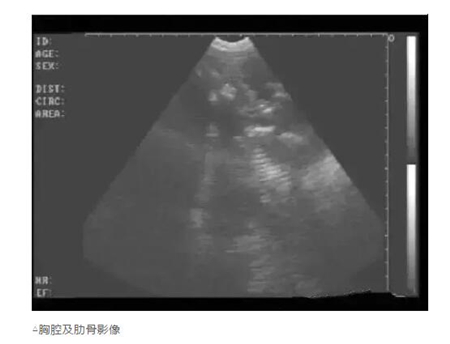

用B超检查母猪妊娠情况,怎样根据显示的图像辨别妊娠状态呢?详细的图文教学分享给大家!